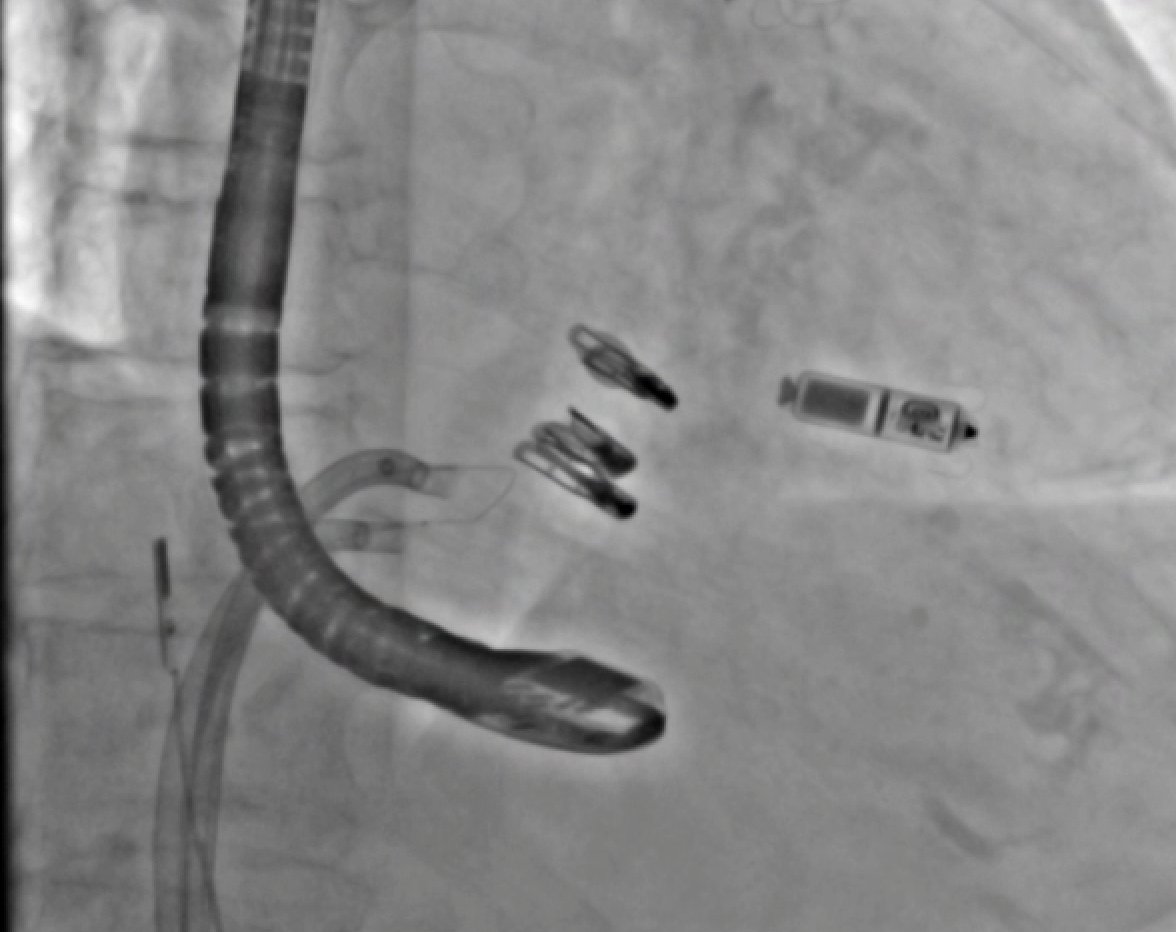

25 days

Just published: Beyond Limits in Alternative Access: The Success of Right Subclavian Transcatheter Mitral Valve Replacement https://t.co/tqabVP6z8e @Brianponeill @PedroMDMSc @engelpedro @GKFram @AhmadJabri8